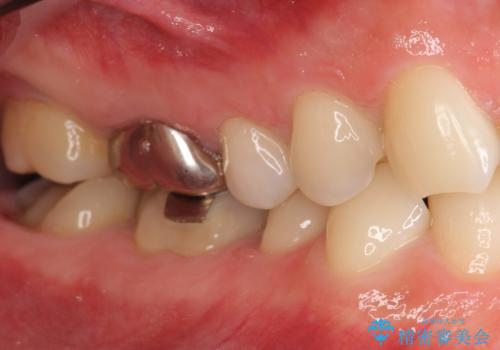

歯頚ラインが変えられないことや天然歯を削るリスクをご理解頂いた上で、オールセラミッククラウンによる補綴治療を行いました。(見えない奥歯のみ天然歯のままとしました)

- ¥2,790,000 (仮歯×24本、根管治療×1本、土台×1本、クラウン×24本、セラミックインレー×1)費用は治療当時の料金となります